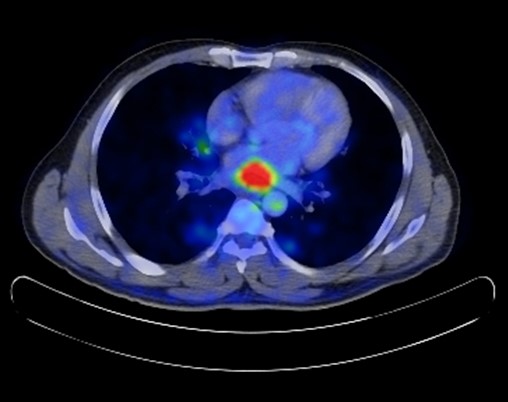

Here we are reporting the case of a 41 years old, male patient who initially presented 5 years back with history of progressive dysphagia and on esophagogastroduodenoscopy a mid to distal stenosing plaque like tumor of the oesophagus was seen and histopathology revealed moderately differentiated squamous cell carcinoma. Endoscopic ultrasound was done and was Staged T3N1 tumor. PET CT shows hyper metabolic mid to distal oesophageal thickening with no distant metastasis (Figure 1).

Figure 1: PET CT scan showing hyper metabolic mid to distal oesophageal thickening.